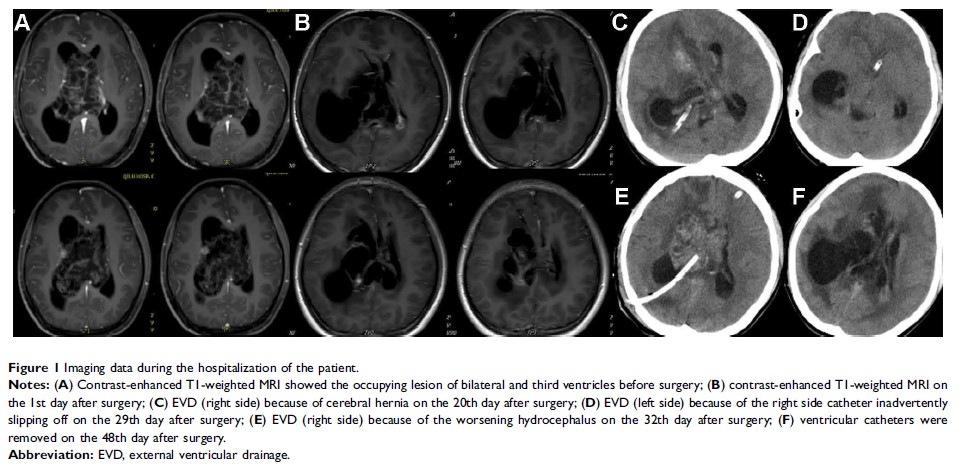

应用静脉注射美罗培南及阿米卡星联合脑室内注射阿米卡星成功治疗碳青霉烯极度耐药的阴沟肠杆菌(MIC≥16mg/L)引起的脑膜炎的病例报告